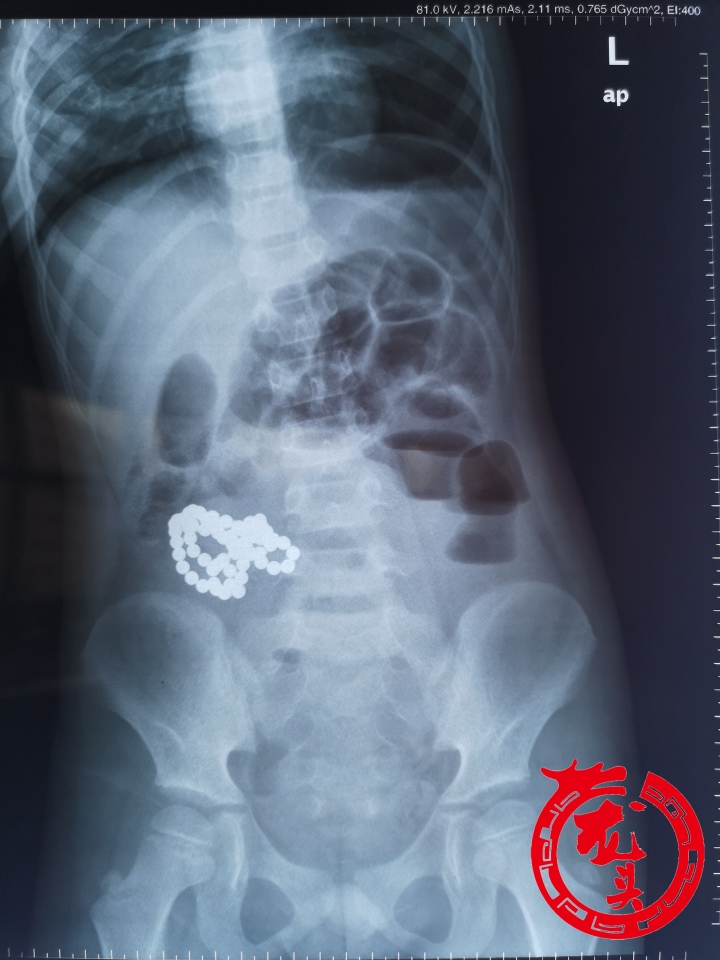

龙头新闻讯(记者 霍营)“一盒巴克球一共64个,孩子吃下去61个,外人乍一看片子还以为是把项链吃了下去,其实是这种磁力很大的巴克球,造成孩子多处肠穿孔、肠梗阻。”回忆起14日凌晨接诊的一名6岁男孩,哈医大二院儿外科徐波教授仍然感到痛心。

14日凌晨,6岁男孩乐乐(化名)因腹痛、呕吐被送往哈医大二院儿外科就诊,医生为乐乐进行X线检查,发现其消化道内有异物,紧急收治入院。

外人从片子上乍一看还以为孩子把项链吃了下去,但医生追问病史时得知,最近乐乐在玩一种叫做巴克球的玩具,12日下午乐乐觉得用手玩不过瘾,出于好奇把巴克球一个接一个地吞进了肚子里,而这一切家长并不知情。

乐乐入院后,儿外科李昭铸主任团队、徐波医生紧急为乐乐进行了各项术前检查,并急诊实施手术。术中,医生通过腹腔镜探查发现,乐乐右下腹小肠聚集,与盲肠粘连紧密,近端肠管扩张梗阻,经脐部扩大切口提出受累部肠管,小肠间断五处穿孔,盲肠一处穿孔。

医生们小心翼翼地将异物取出,清点后发现了61个磁力巴克球。随后,医生将病损部位的两段小肠进行切除,对盲肠进行修补,肠粘连松解,然后完成手术。手术从14日八点半开始,十一点半结束,历时3小时。